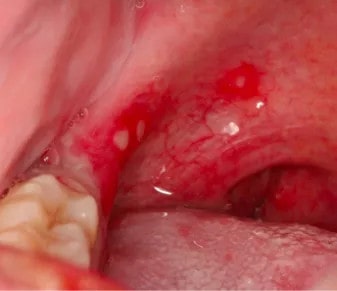

宝宝咽峡部有疱疹,会有明显疼痛感。往往会出现39℃以上的高热,部分宝宝也可能是低热。

疱疹性咽峡炎大多由柯萨奇病毒引起,多见于夏秋季,5~7岁以下儿童更容易感染。